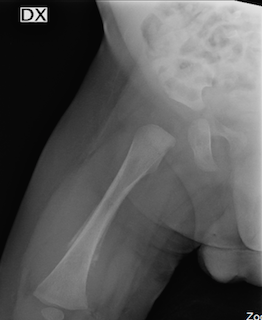

Viene eseguita una radiografia (Rx) di anca e femore destri che mostra una importante reazione periostale al terzo medio-distale del femore con area di rarefazione ossea associata a tumefazione dei tessuti molli adiacenti (Figura 1).

La lesione periostale e l’interessamento dei tessuti molli fanno pensare in primis a una osteomielite, anche se non vi sono né pseudoparalisi né febbre, ma la diagnosi differenziale obbliga a considerare anche la microfrattura da maltrattamento (Rx total body negativa per altre lesioni come risulta anche negativa la ricerca di emorragie retiniche) e, non ultimo, a una malignità.

Il dolore osteoarticolare è frequente all’esordio delle leucemie acute, associato ad altri sintomi nel 40% dei casi, come sintomo principale nel 25%. Più comune nelle leucemie linfoblastiche acute rispetto alle leucemie mieloidi acute, si presenta come dolore osseo diffuso che coinvolge tipicamente le ossa lunghe. L’imaging radiografico si caratterizza per presenza di strie metafisarie, osteolisi, osteosclerosi, osteopenia e, come per il nostro bambino, reazione periostale. Nel nostro caso l’emocromo è stato dirimente, ma in letteratura sono descritti casi, non rari, di esordio con interessamento osseo ed emocromo normale.

Non va quindi dimenticato che, di fronte a un Rx con reazione periostale, la leucemia deve sempre rientrare in diagnosi differenziale.